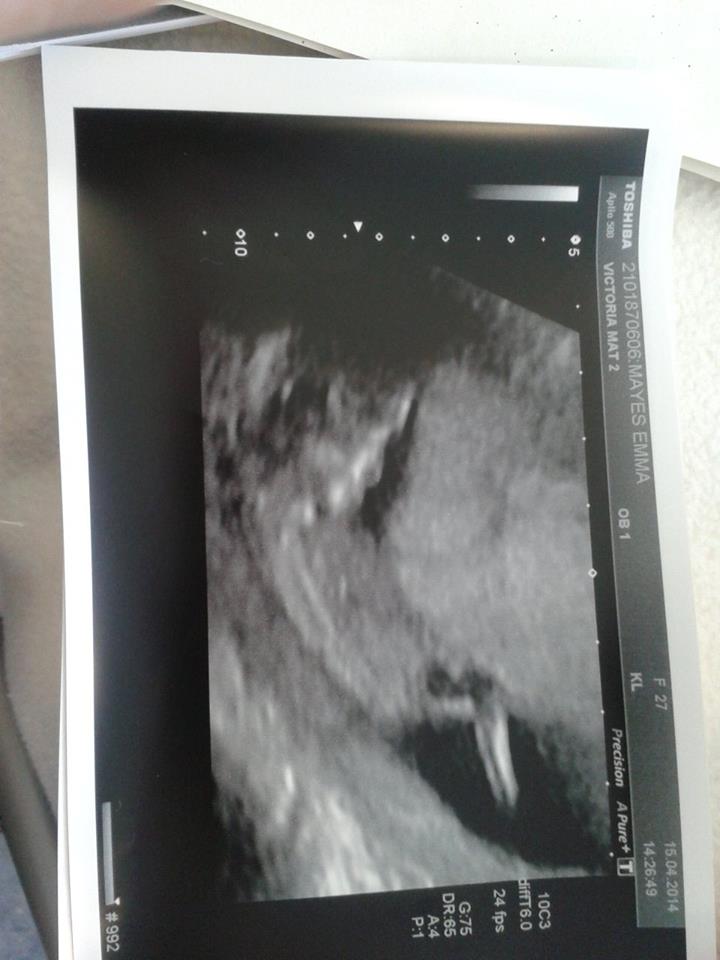

12+1 day have anothe rpicture on here but thought best to start a new thread so you all could see it